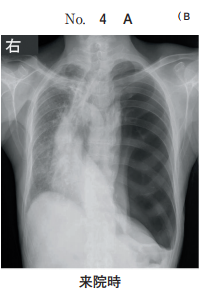

44 64 歳の男性。呼吸困難を主訴に来院した。日前に左胸痛と息切れとが出現し、 次第に増悪してきたため受診した。体温 36.2 ℃。脈拍 100/分、整。血圧 120/80 mmHg。呼吸数 20/分。SpO2 92 %room air 。眼瞼結膜と眼球結膜とに異常を認 めない。頸部リンパ節を触知しない。左胸部に呼吸音を聴取しない。血液所見赤 血球 420 万、Hb 13.0 g/dl、Ht 37 %、白血球 4,400桿状核好中球%、分葉核好 中球 60 %、好酸球%、好塩基球%、単球%、リンパ球 25 % 、血小板 21 万。 CRP 0.4 mg/dl。来院時の胸部エックス線写真別冊No. 4 を別に示す。入院後、 胸腔ドレーンを挿入したところ、直後から咳嗽と泡沫状の喀痰とが出現した。この 時点の胸部エックス線写真別冊No. 4 を別に示す。 胸腔ドレーン挿入後の病態として正しいのはどれか。

(A) 肺 炎 (B) 肺水腫 (C) 無気肺 (D) 肺胞出血 (E) うっ血性心不全